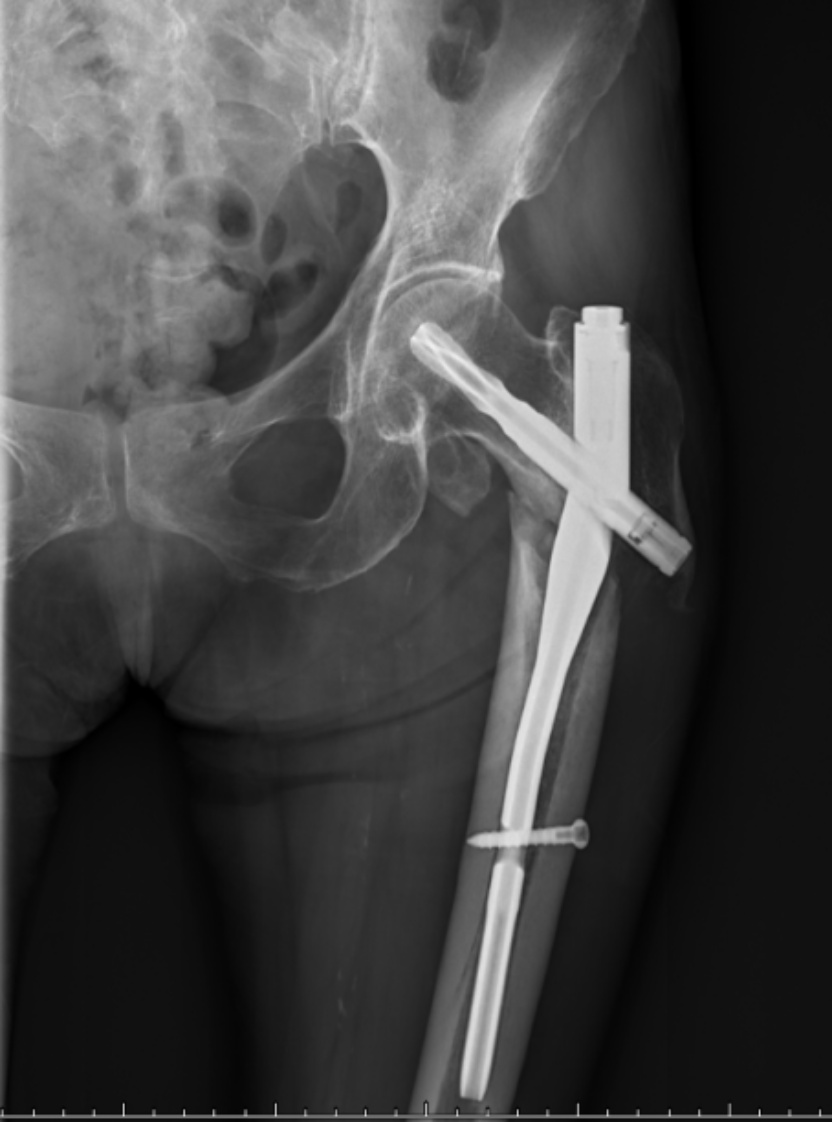

典型病例影像学表现见图1~10。图1为86岁女性右侧股骨转子间骨折(Evans Ⅲ型)患者,术前X线示骨折断端部分错位,术后X线示骨折位置可以及假体位置良好;图2显示了一名81岁男性患者,诊断为左侧股骨转子间骨折,类型为Evans V型,合并股骨干陈旧性骨折。患者接受了生物型加长柄半髋关节置换手术,并进行了股骨近端的钢丝捆扎内固定。术后X线示假体位置良好,股骨近端予钢丝捆扎固定;图3为87岁女性左侧股骨转子间骨折(Evans V型)患者,术后X线示假体位置良好,股骨大小转子骨折位置可,钢丝捆扎固定在位有效;图4为75岁女性左侧股骨转子间骨折(Evans V型)患者,术前X线示左侧股骨转子间骨折PFNA术后、骨折未愈合、内固定断裂。术后假体匹配良好,股骨近端钢丝内固定稳定可靠;图5为75岁男性左侧股骨转子间骨折(Evans IV型)患者,术后股骨大转子出现轻度位移,假体位置正常。图6为87岁男性左侧股骨转子间骨折(Evans V型)患者,给予DAA入路加长柄半髋关节置换,术前X线片,清晰地显示出左侧股骨转子间的骨折情况,术后X线影像,显示股骨的大小转子骨折位置良好,钢丝内固定装置在位稳定,假体位置良好;图7为77岁女性右侧股骨转子间骨折(Evans V型)患者,术前X线片显示右侧股骨转子间存在骨折且股骨大小转子均有累及和移位,术后X线片显示股骨小转子轻度移位,内固定装置位置稳定,假体位置良好;图8为70岁男性左侧股骨转子间骨折(Evans III型)患者,术前的X线片,清晰地显示了左侧股骨转子间的骨折情况,股骨近端髓腔钙化灶,术后假体位置满意;图9为77岁女性右侧股骨转子间骨折(Evans V型)患者,术前X线片,显示右侧股骨转子间及转子下部位骨折情况。术后假体匹配良好;图10为71岁男性右侧股骨颈骨折(Evans IV型)患者,术前X线片,显示右股骨转子间骨折的情况;术后X线表明股骨的大转子和小转子骨折位置保持良好,内固定装置稳固,术后假体位置正常。

(a) (b)

Figure 2. An 81-year-old male patient with left intertrochanteric fracture of the femur (Evans type IV). (a) Before surgery; (b) After surgery

2. 81岁男性左侧股骨转子间骨折(Evans Ⅳ型)患者。(a) 术前;(b) 术后